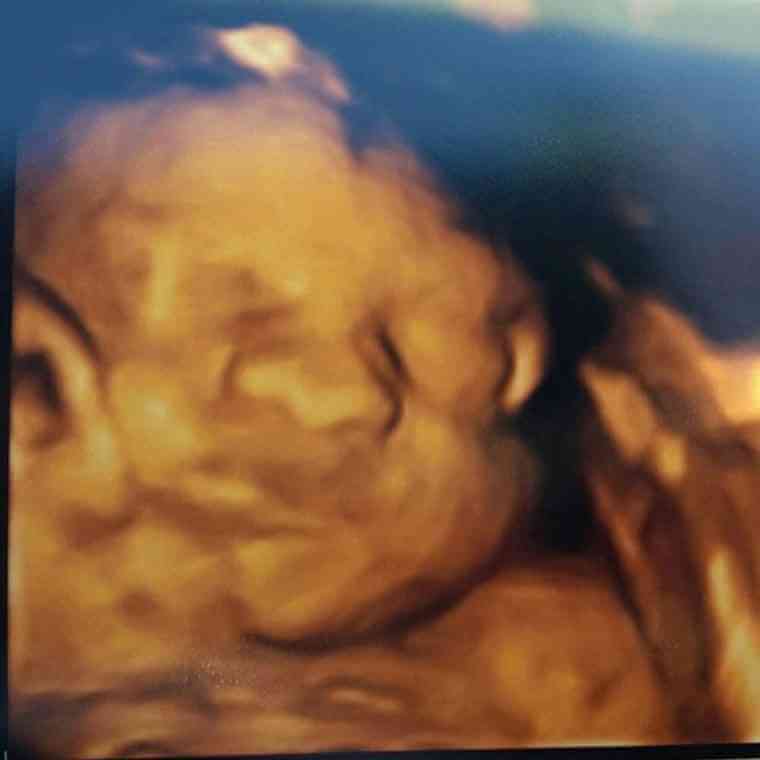

Neste caso, vamos falar de Holly Hodson, uma mulher que estava ansiosa e maravilhada por estar prestes a ter o seu filho nos braços. Contudo, no ultrassom que fez aos oito meses gestacionais, algo parecia estar mal…

Foi comunicado a esta futura mamã que o seu filho tinha uma doença complicada. Tratava-se de gastrosquise, que é uma má-formação com origem numa falha no desenvolvimento da parede do abdômen – o que levou a que o feto tivesse uma entrada na zona abdominal. Desta forma, o seu estômago e os seus intestinos não estavam dentro do corpo, mas sim fora. A sugestão imediata do médico foi que Holly abortasse, pois, na sua opinião, Teddy não tinha hipóteses de resistir.